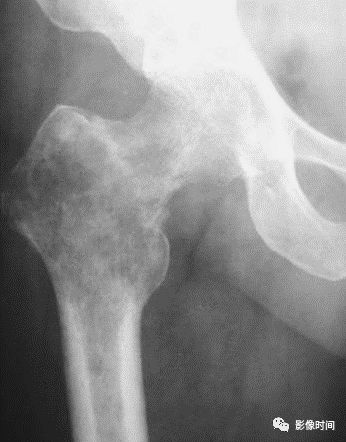

(一)地图样破坏  地图样破坏是指肿瘤组织在一个局部呈团块状生长造成界限清楚的骨质破坏(图 1、图 2、图 3、图 4)。

病灶可位于骨的中心或一侧部位,呈圆形、卵圆形密度减低区,与正常骨质分界清晰,边缘可有或无硬化带围绕,骨的形态无变化,病灶内可完全透亮或可见粗细不均、大小不等的残留骨嵴,内缘可光滑或呈分叶状压迹。

地图样破坏见于大多数良性肿瘤和肿瘤样病变如单纯性骨囊肿、骨纤维结构不良、血管瘤等、也可见于部分恶性骨肿瘤如骨转移瘤、骨髓瘤等。

图 2  地图样破坏:骨纤维结构不良